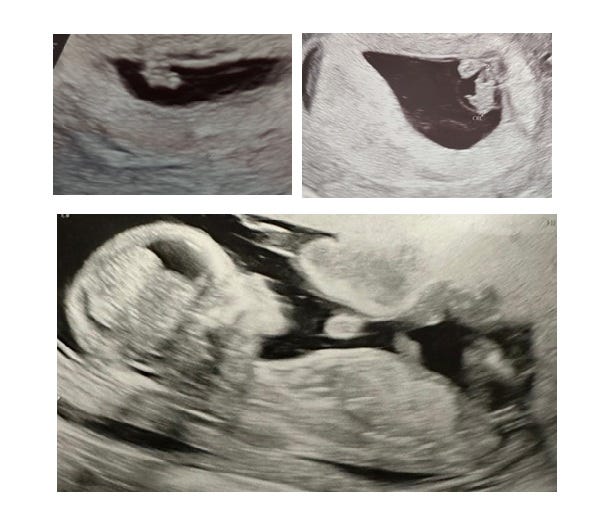

When people ask if you’re a boy or girl, I mainly think…Christ, I don’t even know if it’s human. The movements we see as you swim around my abdomen every evening more suggest you’re going to come bursting out of my stomach like the alien in Alien. It’s definitely more creepy than it is magical.